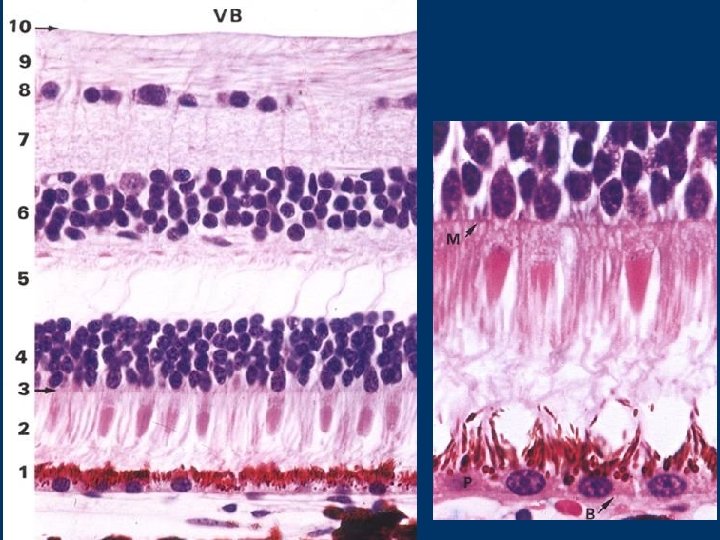

cells described above show layered (laminated) organization in the retina in direction from the Bruch´s membrane to the vitreous space, 10 distinct layers are to distinguish 1. Pigment epithelium (layer) 2. Layer of rods and cones = the peripheral parts of the rod a cone cells 3. External limiting membrane = outer bases of Müller cells THE 1 ST NEURON 4. External nuclear layer= nuclei of rod and cone cells 5. External plexiform layer - contains synapses between the rod (cone) cells and bipolar cells 6. Internal nuclear layer= bipolar cells (it also contains nuclei of Müller cells, bodies of horizontal and amacrine cells) THE 2 ND NEURON 7. Internal plexiform layer - contains synapses between the bipolar and ganglion cells 8. Ganglion cell layer = bodies of multipolar neurons THE 3 RD NEURON 9. Nerve fiber layer = axons of multipolar neurons converging to blind spot 10. Internal limiting membrane = inner bases of Müller cells

Human retina (similar to retina of all vertebrates) is inverse e. g. light must pass through most layers of retina (in all, through 7 layers from 10 th to 3 rd ones) than is absorbed of peripheral parts of rods and cones